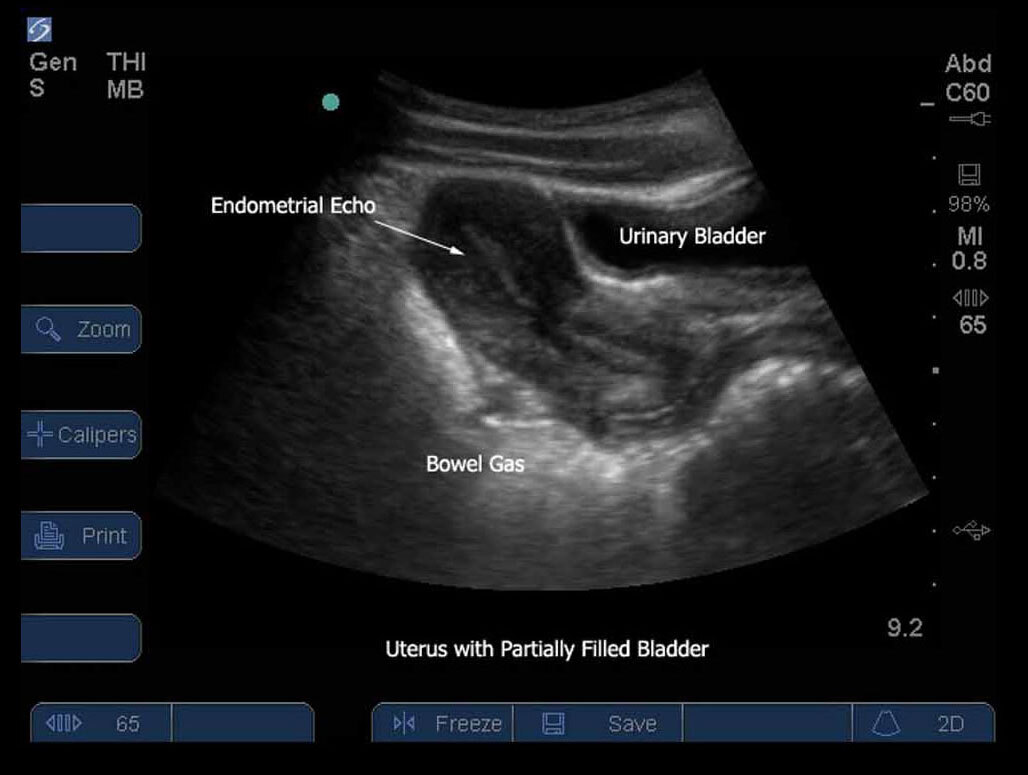

膀胱が充満していない子宮

子宮内膜のエコー

腸内ガス

膀胱